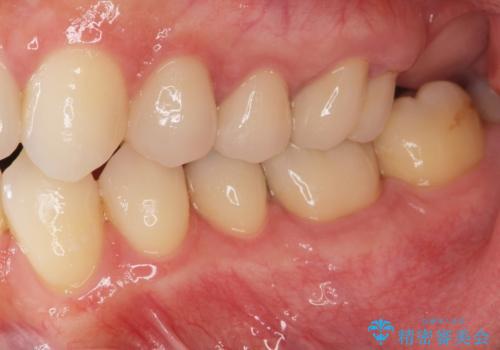

- 突き出た前歯の角度の改善と虫歯治療の改善を求めて来院されました。

虫歯を除去したのち、マウスピース矯正治療を行い、歯並びやがたつきを改善したのち、セラミックに置き換えることで審美性の向上を計画します。

矯正や虫歯治療、セラミック治療といった複合的な治療を一医院で行うことができるのが当法人の大きな特長です。